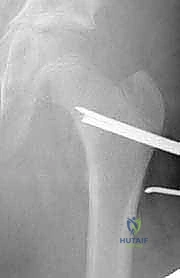

6. إدخال الشريحة والتثبيت (Plate Insertion & Fixation)

يتم إدخال نصل الشريحة ذات الزاوية 90 درجة في المسار الذي تم تحضيره في عنق الفخذ. ثم يتم ضم جزئي العظم المقطوعين معاً (إغلاق الفجوة)، مما يؤدي فوراً إلى تغيير زاوية عنق الفخذ إلى الوضع الطبيعي الجديد. يتم تثبيت الجزء الطويل من الشريحة على جسم عظم الفخذ باستخدام براغي قوية من التيتانيوم أو الفولاذ الطبي المقاوم للصدأ.

لماذا الشريحة ذات الزاوية 90 درجة (90-Degree Blade Plate) تحديداً؟

قد يتساءل البعض: لماذا يصر الأستاذ الدكتور محمد هطيف على استخدام هذا النوع المحدد من الشرائح في عمليات قطع عظم الفخذ الداني التقويمي؟ الإجابة تكمن في الميكانيكا الهندسية:

- التثبيت فائق الصلابة (Rigid Fixation): النصل العريض للشريحة الذي يدخل في عنق الفخذ يوفر ثباتاً دورانياً وزاوياً لا مثيل له، مما يمنع العظمة من التحرك أثناء فترة الالتئام.

- التحكم الدقيق في الزوايا ثلاثية الأبعاد: تسمح هذه الشريحة بتصحيح زاوية الميل (Varus)، وكذلك تصحيح الدوران الخاطئ للعظمة (Derotation) في نفس الوقت.